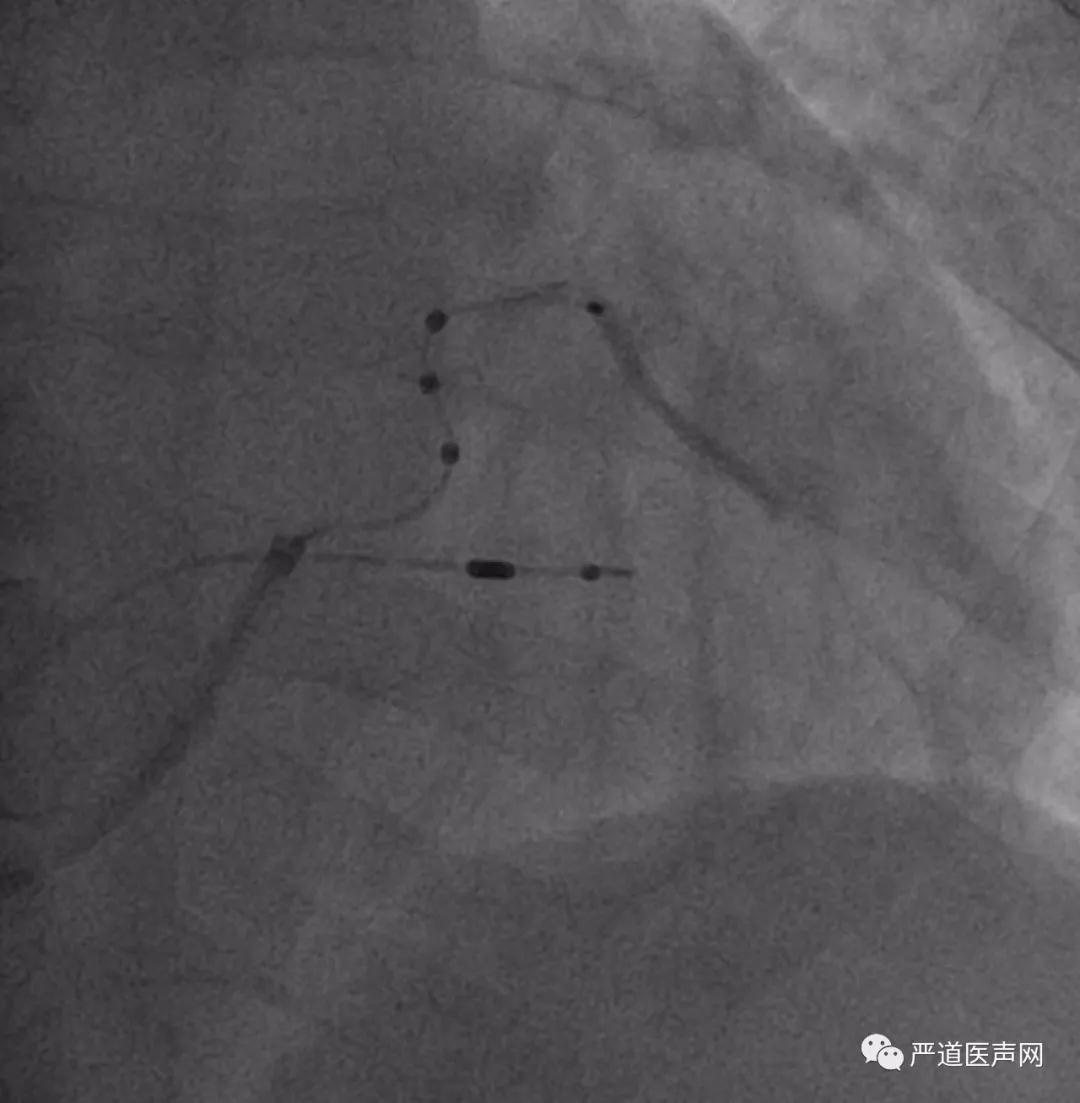

术中造影

导线头端直接造影

术中,徐健教授根据本例患者的血管情况对CRT植入过程中可能会使用到的一些工具和小技巧向学员们进行了详细的讲解。对于该病例,徐健教授采用Amplatz+泥鳅导丝的方法寻找并顺利进入冠状窦,由于患者侧静脉的近端部分存在一定程度扭曲,徐健教授采用两种不同硬度的导丝,顺利的将ACUITY X4 Spiral S左室四极导线送入了血管的远端。